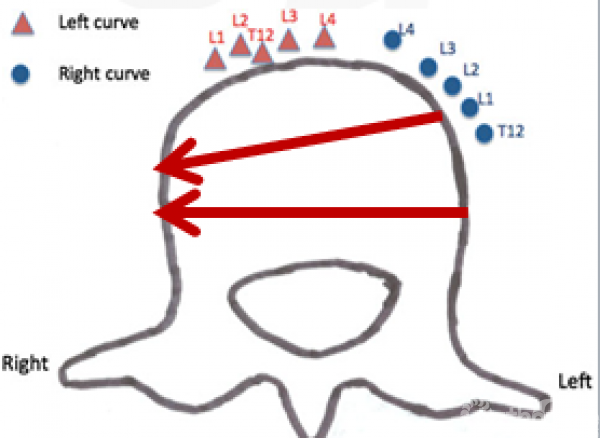

Jun Qiao等人[9]研究发现由于脊柱两侧的大血管分布存在差异,左侧的主动脉壁厚弹性较好,不易致钝性损伤;右侧的下腔静脉壁薄弹性较差,容易损伤。

同时他们通过CT观察发现左与右侧凸的胸腰弯/腰弯AIS患者主动脉与脊椎的相对位置存在差异,由于脊椎向凸侧旋转,在左侧凸患者中,主动脉从正常时的椎体左侧旋转至椎体前方偏右的位置;而在右侧凸中,主动脉向椎体左后方旋转,这预示在右侧凸患者中,椎体置钉时主动脉损伤的风险更高。

图9.左侧凸椎体钉与主动脉位置关系

图10.右侧凸椎体钉与主动脉位置关系